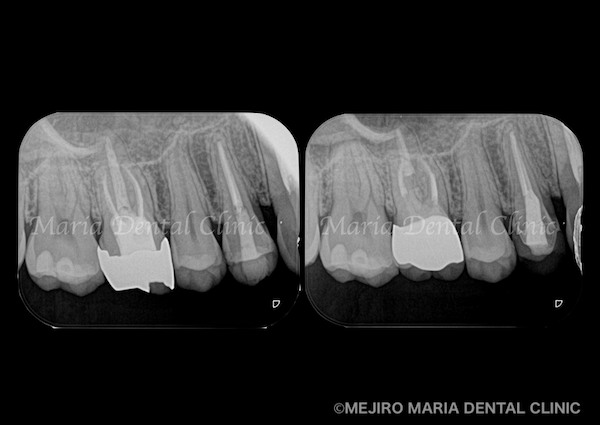

【症例】被せ物の前に行う予防的な根管治療